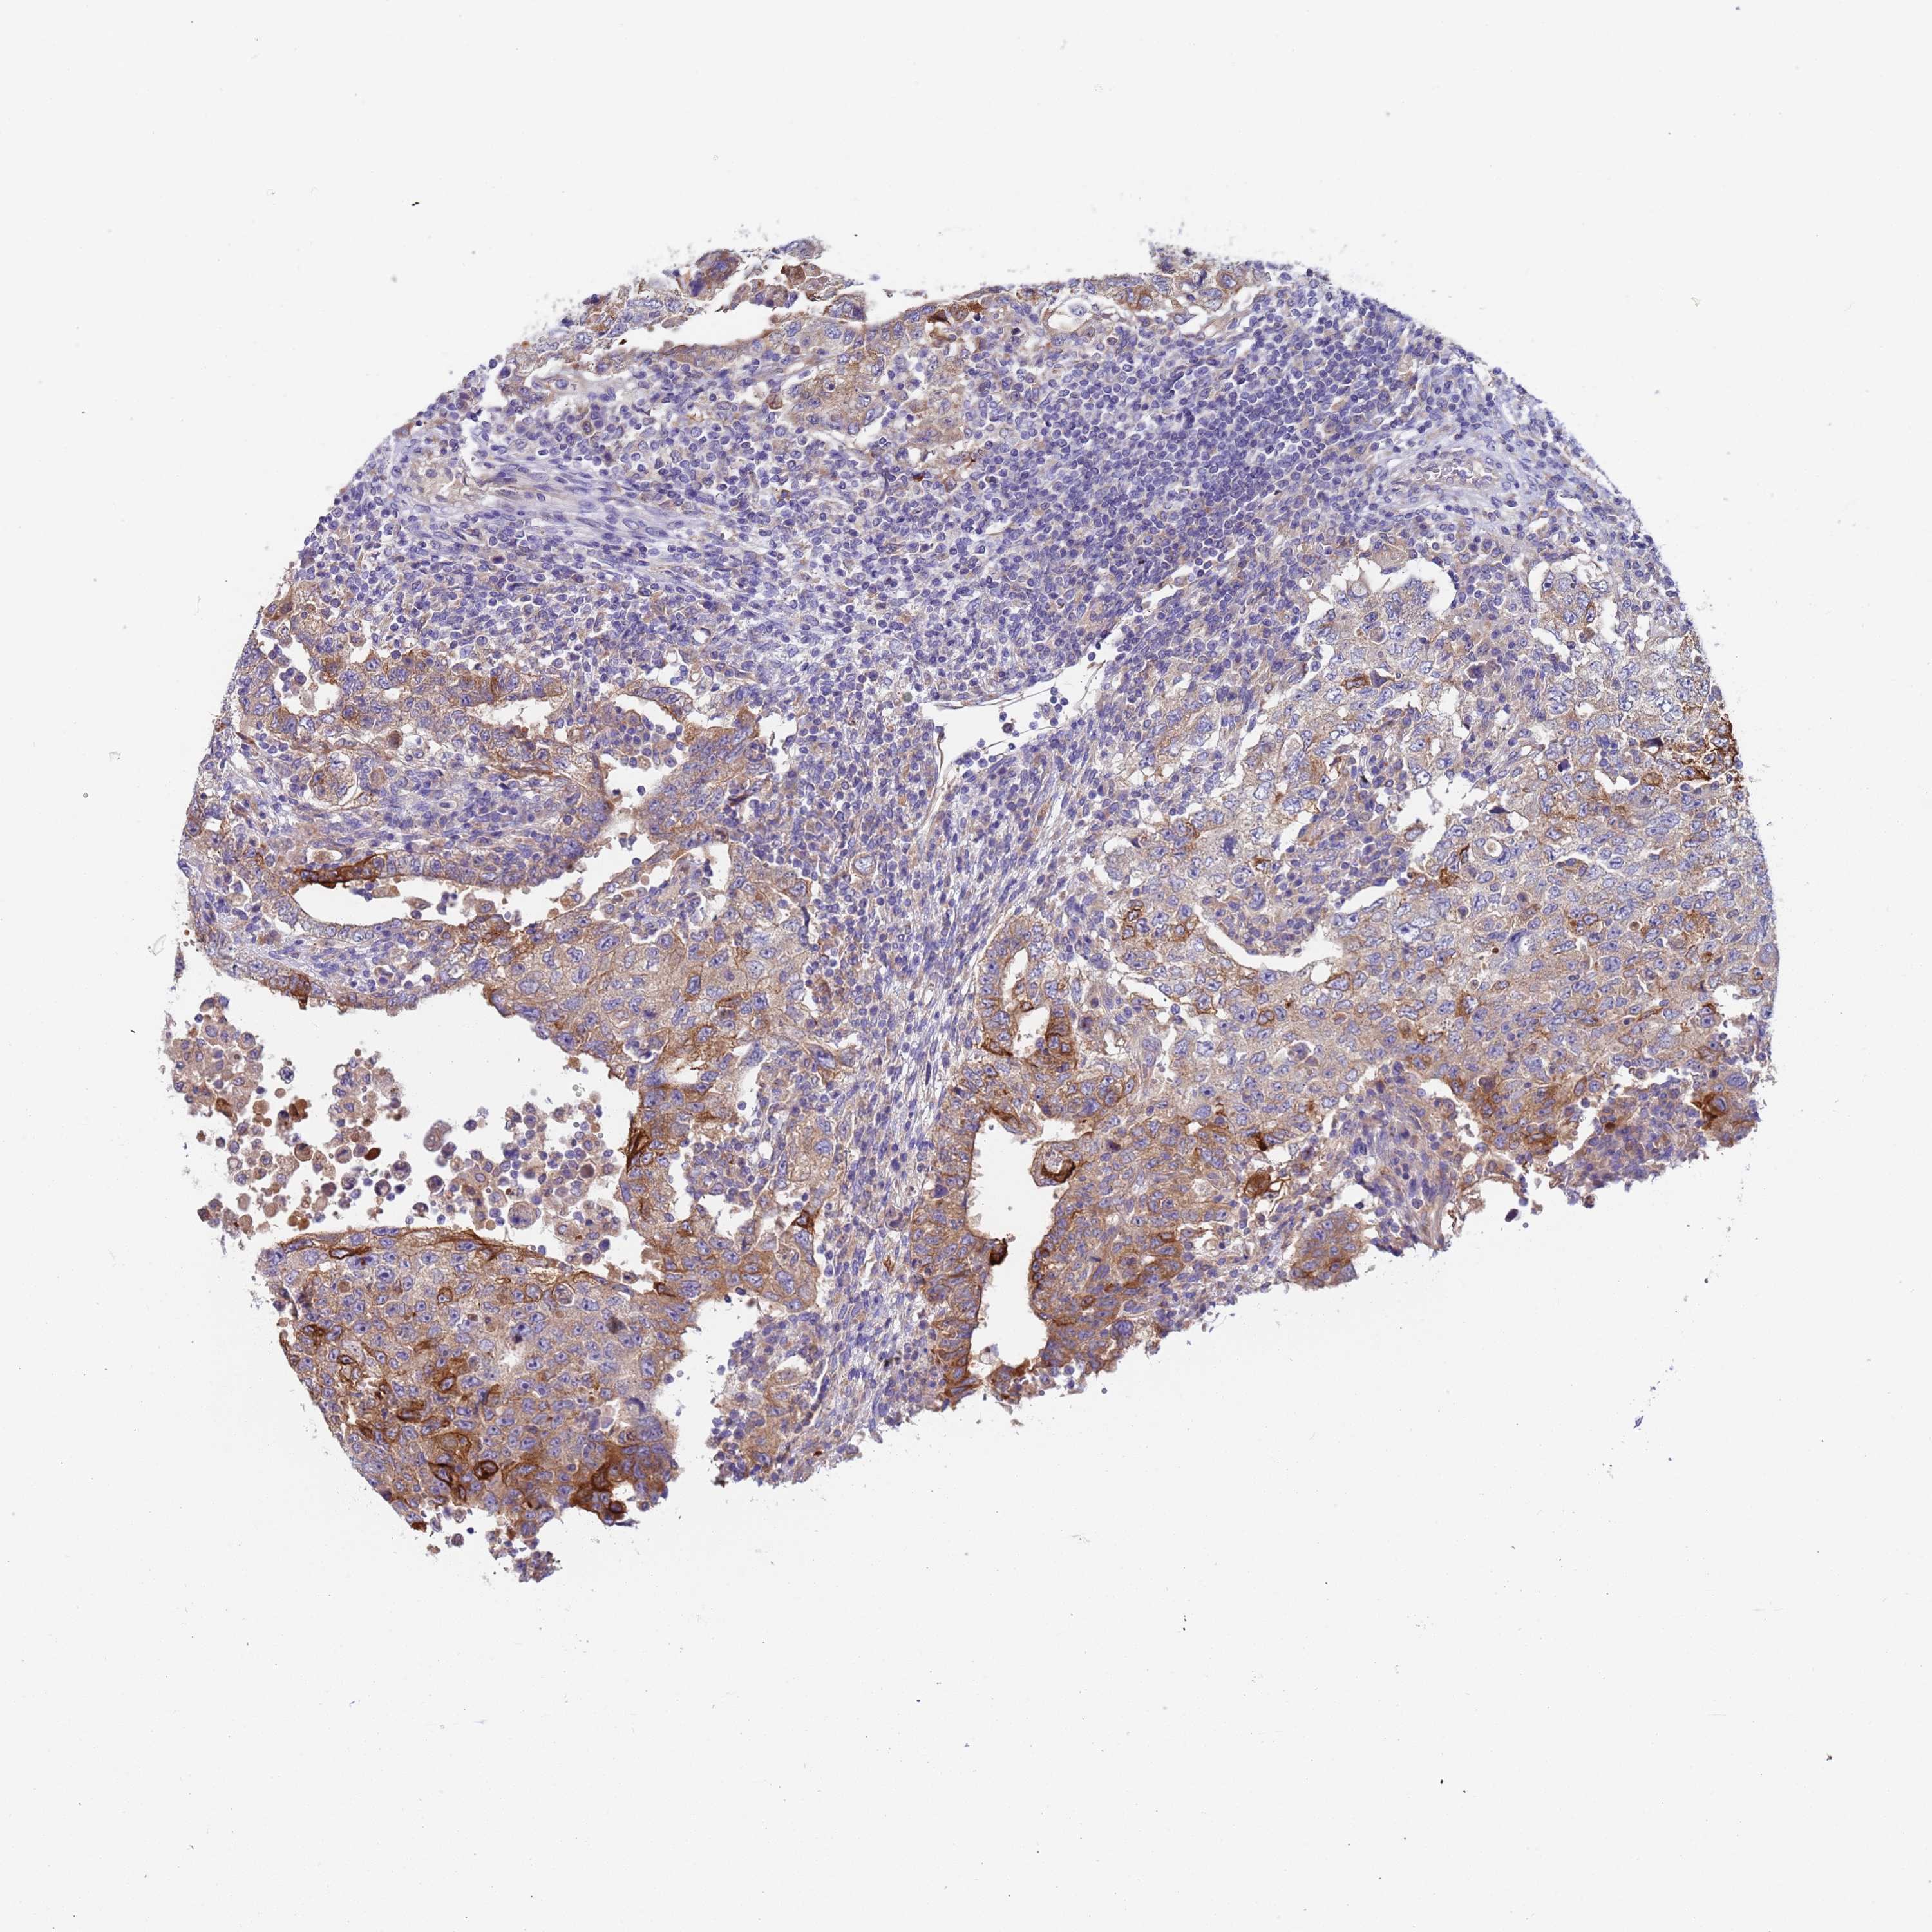

TESTIS CANCER - Protein expressioni

A mouse-over function shows sample information and annotation data. Click on an image to view it in a full screen mode. Samples can be filtered based on level of antibody staining by selecting one or several of the following categories: high, medium, low and not detected. The assay and annotation is described here.

Note that samples used for immunohistochemistry by the Human Protein Atlas do not correspond to samples in the TCGA dataset.

Antibody stainingi

Antibody staining in the annotated cell types in the current human tissue is reported as not detected, low, medium, or high, based on conventional immunohistochemistry profiling in selected tissues. This score is based on the combination of the staining intensity and fraction of stained cells.

Each image is clickable and will lead to virtual microscopy that enables deeper exploration of all samples and also displays staining intensity scores, fraction scores and subcellular localization as well as patient and tissue information for each sample.

Antibody HPA046936

Staining

High

Medium

Low

Not detected

Intensity

Strong

Moderate

Weak

Negative

Quantity

>75%

75%-25%

<25%

None

Location

Nuclear

Cytoplasmic/membranous

Cytoplasmic/membranous,nuclear

Carcinoma, Embryonal, NOS

Seminoma, NOS